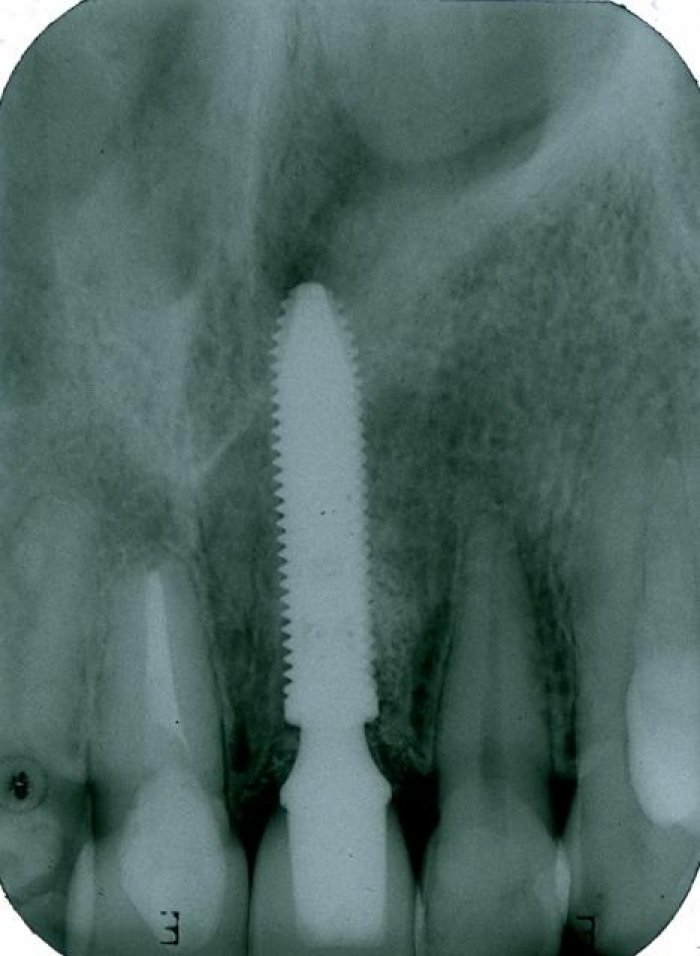

Raio X com dente de porcelana instalado

Imagem final do caso terminado em janeiro de 2013